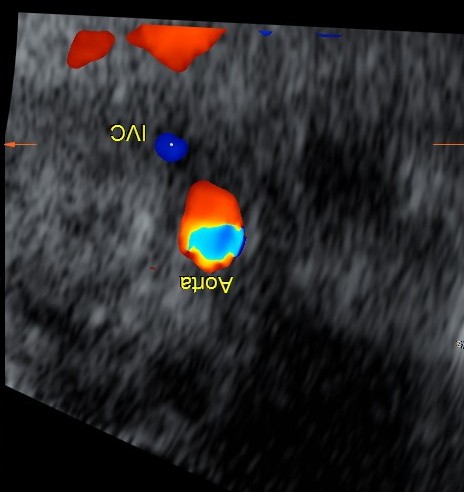

The relationship among the inferior vena cava, aorta, and spine displayed by ultrasonography has been shown to be a reliable method to diagnose situs in the newborn. This technique can be applied to the fetus in utero as well.

Normally, the aorta lies to the left of the spine and the inferior vena cava lies to the right. The following image shows the normal situs in a fetus , with head in upper pole.

Right isomerism or asplenia is suggested when the aorta and vena cava are found together on the same side of the spine.